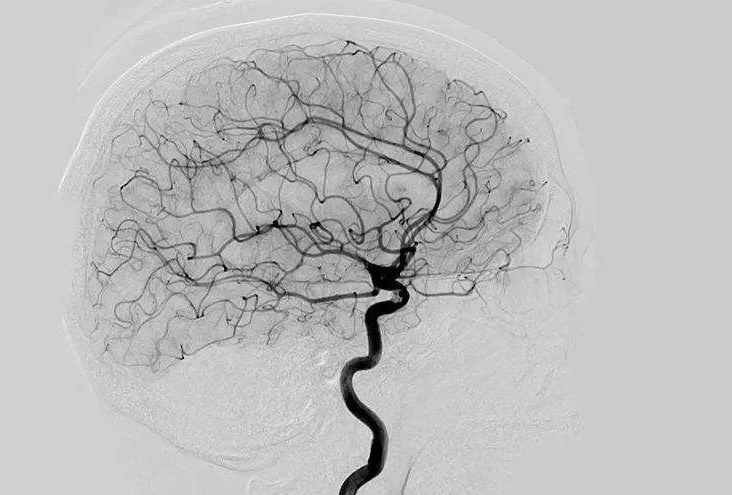

Digital Subtraction Angiography 血管造影機(jī)應(yīng)注意什么?

Digital Subtraction Angiography 血管造影機(jī)又稱數(shù)字減影血管造影機(jī),是通過(guò)電子計(jì)算機(jī)進(jìn)行輔助成像的血管造影方法,應(yīng)用計(jì)算機(jī)程序進(jìn)行兩次成像完成的。在注人造影劑之前,第一次成像工作,圖像轉(zhuǎn)成數(shù)字信號(hào)儲(chǔ)存,注人造影劑后,再次成像并轉(zhuǎn)換成數(shù)字信號(hào),兩次數(shù)字相減,消除相同的信號(hào),得到只有造影劑的血管圖像。臨床主要應(yīng)用于冠心病、心律失常、瓣膜病和先天性心臟病的診斷和治療。